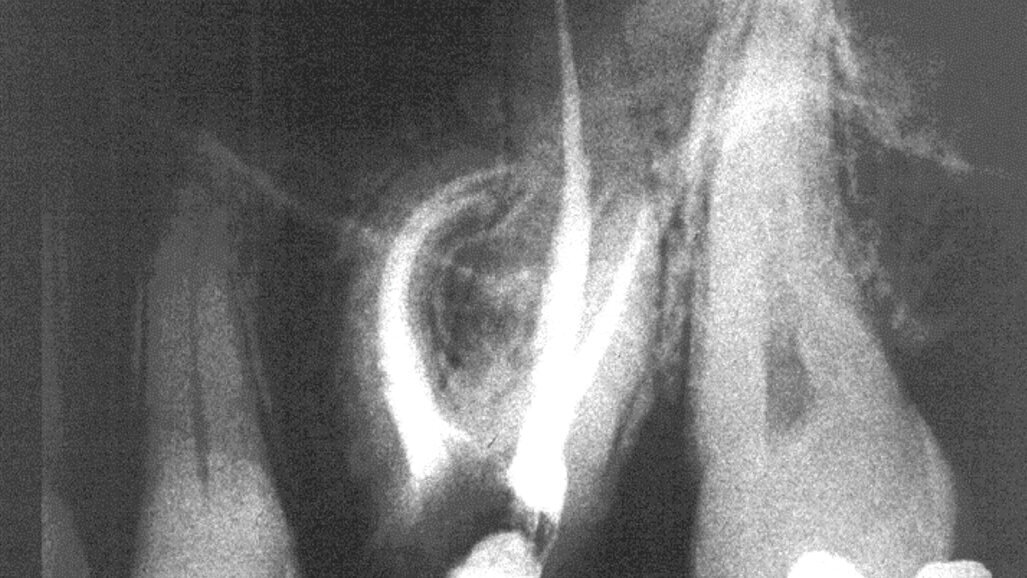

Proširivači sa manjim brojem navoja se koriste na način koji omogućava njihovu dugotrajnu upotrebu, praktično eliminišući mogućnost loma instrumenta, dajući stomatologu znatno pouzdanije informacije potrebne za odluku do koje širine treba treba obraditi kanal, sa mogućnošću da se koriste i kao ručni i kao mašinski instrumenti. Njihovo korišćenje na ovaj način nalazi sve veću podršku u stručnoj literaturi u kojoj je dokazano da je moguće postići bolje rezultate u poređenju sa korišćenjem NiTi rotirajućih instrumenata, dok je cena niža za 90%. Zbog toga ne iznenađuje činjenica da ovaj alternativni pristup privlači sve veću pažnju. Klinički slučajevi su prikazani na slikama 5, 6 i 7.